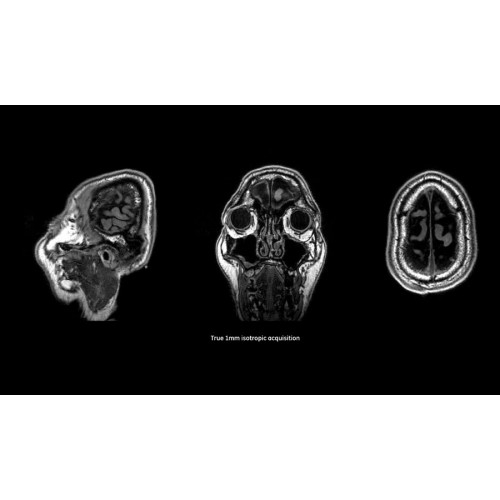

Детализация изображений

Система SIGNA Pioneer воплощает поразительные достижения в области визуализации. Передовая технология Total Digital Imaging (TDI) позволяет добиться большей четкости изображений и на четверть повысить соотношение сигнал/шум.

Помимо технологии 97 РЧ-каналов, SIGNA Pioneer использует магнит 3.0Т высокой однородности, предназначенный для повышения качества визуализации во всех областях, а также закладывающий прочный фундамент для долгосрочных инвестиций и роста клинических возможностей.